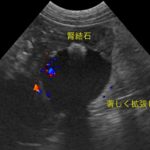

かかりつけ医で定期的に超音波検査で腎結石のモニターをしていたところ、急に腎盂が拡張してきたので早急に対応して欲しいと連絡がありました。尿管結石により尿路閉塞が起こっていました。マイクロサージェリーで尿管を2箇所切開し、尿管結石を摘除しました。術後の狭窄予防に一時的に尿管ステントを留置しています。術後翌日から、腎盂拡張は解消しましたが、術後の経過により、生体にとって異物となる尿管ステントは抜去する予定です。